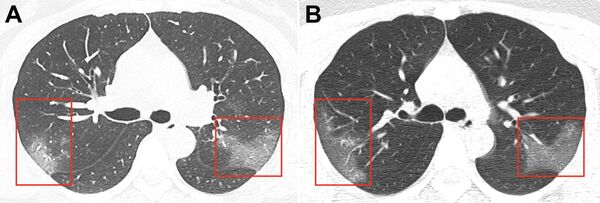

Com base nas caraterísticas epidemiológicas, sintomas clínicos e resultados da tomografia, foi diagnosticada com pneumonia do tipo 2019-nCoV. Após três dias de tratamento, a área afetada dos pulmões aumentou (foto B).